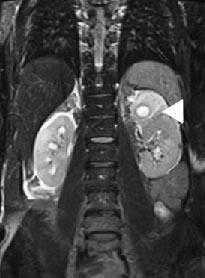

Гидронефротическая трансформация левой почки III ст, паренхима почки визуализируется в виде тонкого ободка, толщиной до 0,1-0,2 см, резко атрофична. Стеноз лоханочно-мочеточникового сегмента слева (хроническая обструктивная уропатия), (стрелка).

МР-урография показывает преимущественно кистозное поражение (стрелка) в верхнем полюсе левой почки с отеком.